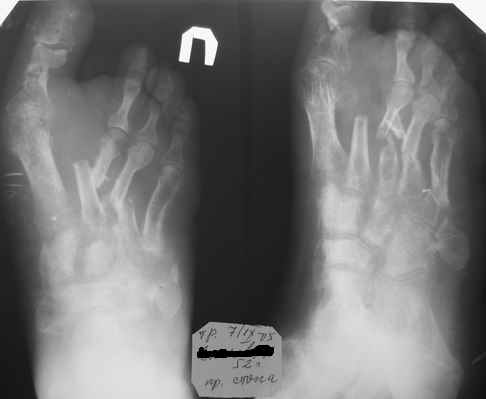

Здравствуйте, Тимур Вячеславович. Спасибо за живой интерес к проблеме: этапы к Вам понял. Насчет ампутации, я думаю, что больной еще не созрел, наоборот- полон оптимизма. Вот свежие рентгенограммы и стопа на 5 день после операции. Появились грануляции, но рана глубокая- 2-2,5 см. Хотелось бы узнать о Вашей тактике на ближайший период, если это возможно. С уважением, Алексей